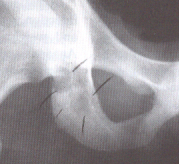

This is a picture of a persons hip. It is marked so you can see what appears to be a disappearance of bone density, which it is.

This kind of yeast infection is actually quite frequent and occurs in 10-42% of people that have been immuno-compromised by diabetes, renal failure, and immuno-suppressive therapies such as corticosteroids.